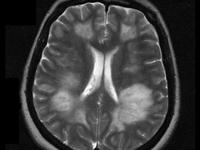

急性播散性脑脊髓炎是特发性中枢神经系统脱髓鞘病的一种,儿童多见,但亦可发生于任何年龄。ADEM是急性或亚急性起病的伴有脑病(行为异常或意识障碍)表现的、影响中枢神经系统多个区域的首次发生的脱髓鞘疾病。急性播散性脑脊髓炎是怎么回事?接下来跟大家分享下我的看法。

相关图片